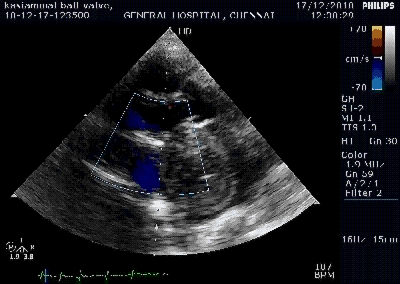

* The direction and the width of MR jet is related to the mechanism of MR.

If there is chordal shortening due to fibrosis of mitral valve co -optation plane is altered . The degree of chordal shortening , pap muscle fibrosis (rare) symmetry of chordal involvement determine the MR.

The sail like AML commonly directs the jet posteriorly and laterally .(Murmur conducted to axilla and back )

It is rare for PML to prolapse in RHD , if it does occur , it directs the jet anteriorly (murmur conducted to aortic area mimic AS !)

It is rare to see a perfect central jet in RHD . presence of Central jet is a good sign to consider mitral valve repair.